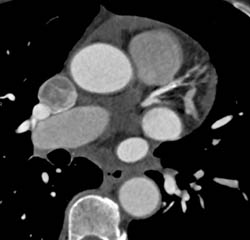

Calcified Plaque LAD in Various Perspectives